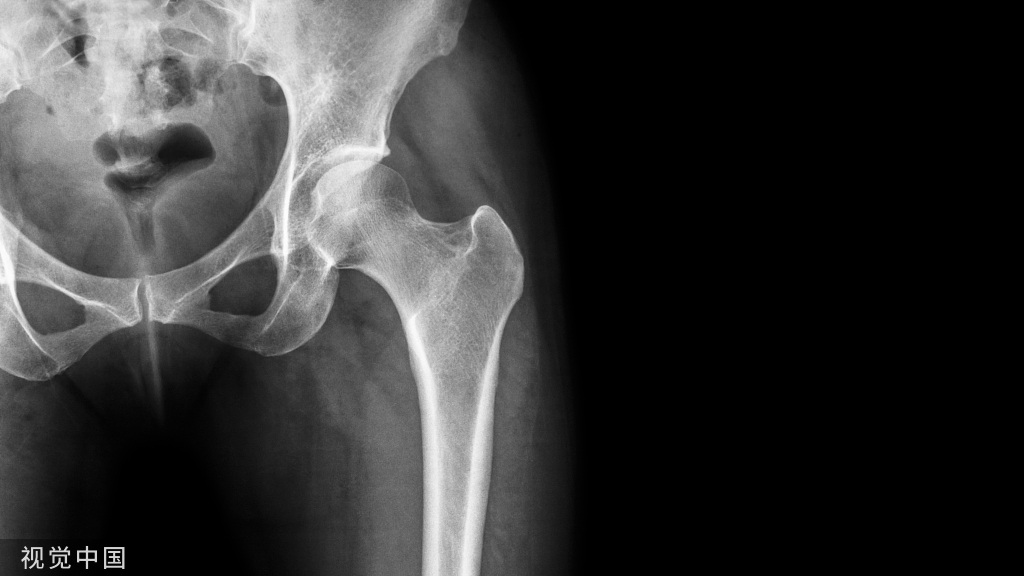

1、低血磷、ALP高、血钙正常、低骨密度可能为骨软化(假骨折等,特征骨骼表现、肌无力);

2、高血钙、ALP高、低骨密度可能为甲旁亢(PTH升高、特征骨骼表现、B超、ECT);

3、PTH低或者正常可能为转移性骨骼肿瘤;

4、低骨密度、骨折可能为多发性骨髓瘤(蛋白尿、异常免疫球蛋白、骨穿);